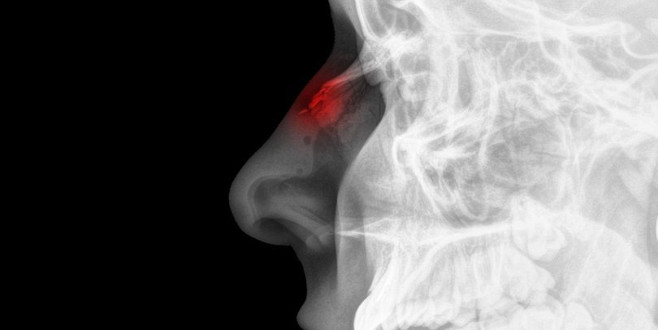

Genellikle darp veya trafik kazası gibi travmalar sonucunda oluşan burun kırıklarına hızlı müdahale edilmemesi kişiye sıkıntı yaratabilir.

Burun kırıkları genellikle darp veya trafik kazası gibi travmalar sonucunda oluşurlar. Bir burun kırığı ilk oluştuğu anda, burnun dış kısmındaki, burnun dışındaki piramidi oluşturan kemikler yerinden oynayabilir veya ilk anlarda ödemin etkisiyle kırığın şiddeti tam anlaşılamayabilir. Genellikle bu tarz vakalarda mutlaka bunun dışında bir şişlik veya yara ödem gözükmese bile mutlaka burnun iç kısmının detaylı muayenesi yapılır. Çünkü burnu kıracak kadar şiddetli bir darbe, burnun iç kısmında da duvarı kırabilir ve kanamalara sebep olabilir. Bu tarz durumlarda burun kırığı durumunda yapılması gereken şey; o kırık parçaların mümkün olan en hızlı şekilde yerine getirilip, yerleştirilmesidir.

“Burun içindeki eğriliklerin veya hematom dediğimiz kan oturmasında hızlı bir şekilde boşaltılması gerekir” diyen Dr. Öğr. Üyesi Denizhan Dizdar, “Ancak bu tarz durumlarda gerekirse ödemin şişinin inmesi ve hastanın anestezi alabilecek duruma gelmesi için 48 saate kadar bekleme seçeneğinde mevcuttur. Bu tarz burun kırığı düzeltmeleri genellikle anestezi altında yapılır. Ameliyathanede hem burnun kırık olan fragmanlarının yerine yerleştirilmesi, hem de içerde olan eğriliklerin düzeltmesi yapılacaktır. Ameliyat sonrasında burun sırtında bir atel alçı olması beklenir. Morluklar, şişlikler olma ihtimali çok yüksektir burun kırıklarında ve daha sonrasında bu atel bir hafta sonrasına yaklaşık alınacaktır. Ancak kırılmış burun kemiğinin tam düzelmesi muhtemelen 6- 9 ayı hatta bazen 1 yılı bile bulabilir. Tabi bu tarz burun kırıklarında estetik anlamda görünüşle alakalı bir bozulma olması da mümkündür. Aynı esnada deneyimli bir doktorun bu şekli düzeltmesi de uygun olacaktır” dedi.

Burun kırılması durumunda ilk yapılması gereken şey mümkünse hemen bölgeye buzla soğuk kompres uygulamak ve olabildiğince çabuk bir şekilde Kulak Burun Boğaz uzmanına başvurmaktır. Kırık olan burnu kendiniz düzeltmeyi denemeyin. Çünkü ciddi sonuçlar doğurabilir. Burnu düzeltmek isterken kişinin tansiyonu düşüp, bayılıp çok daha başka sıkıntılara sebep olabilir.